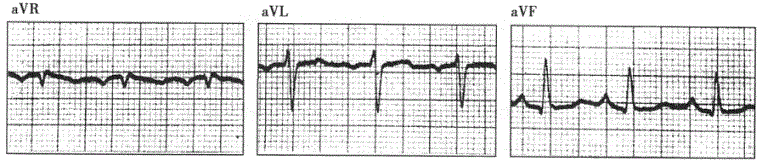

问题 患者女性,76岁,慢性咳喘33年,临床诊断慢性肺源性心脏病。心电图检查如下图所示。 ? ? ? 为了明确诊断,应首选的检查是

选项 A.动态心电图 B.运动平板试验 C.心肌灌注显像 D.冠状动脉造影 E.超声心动图

答案 E